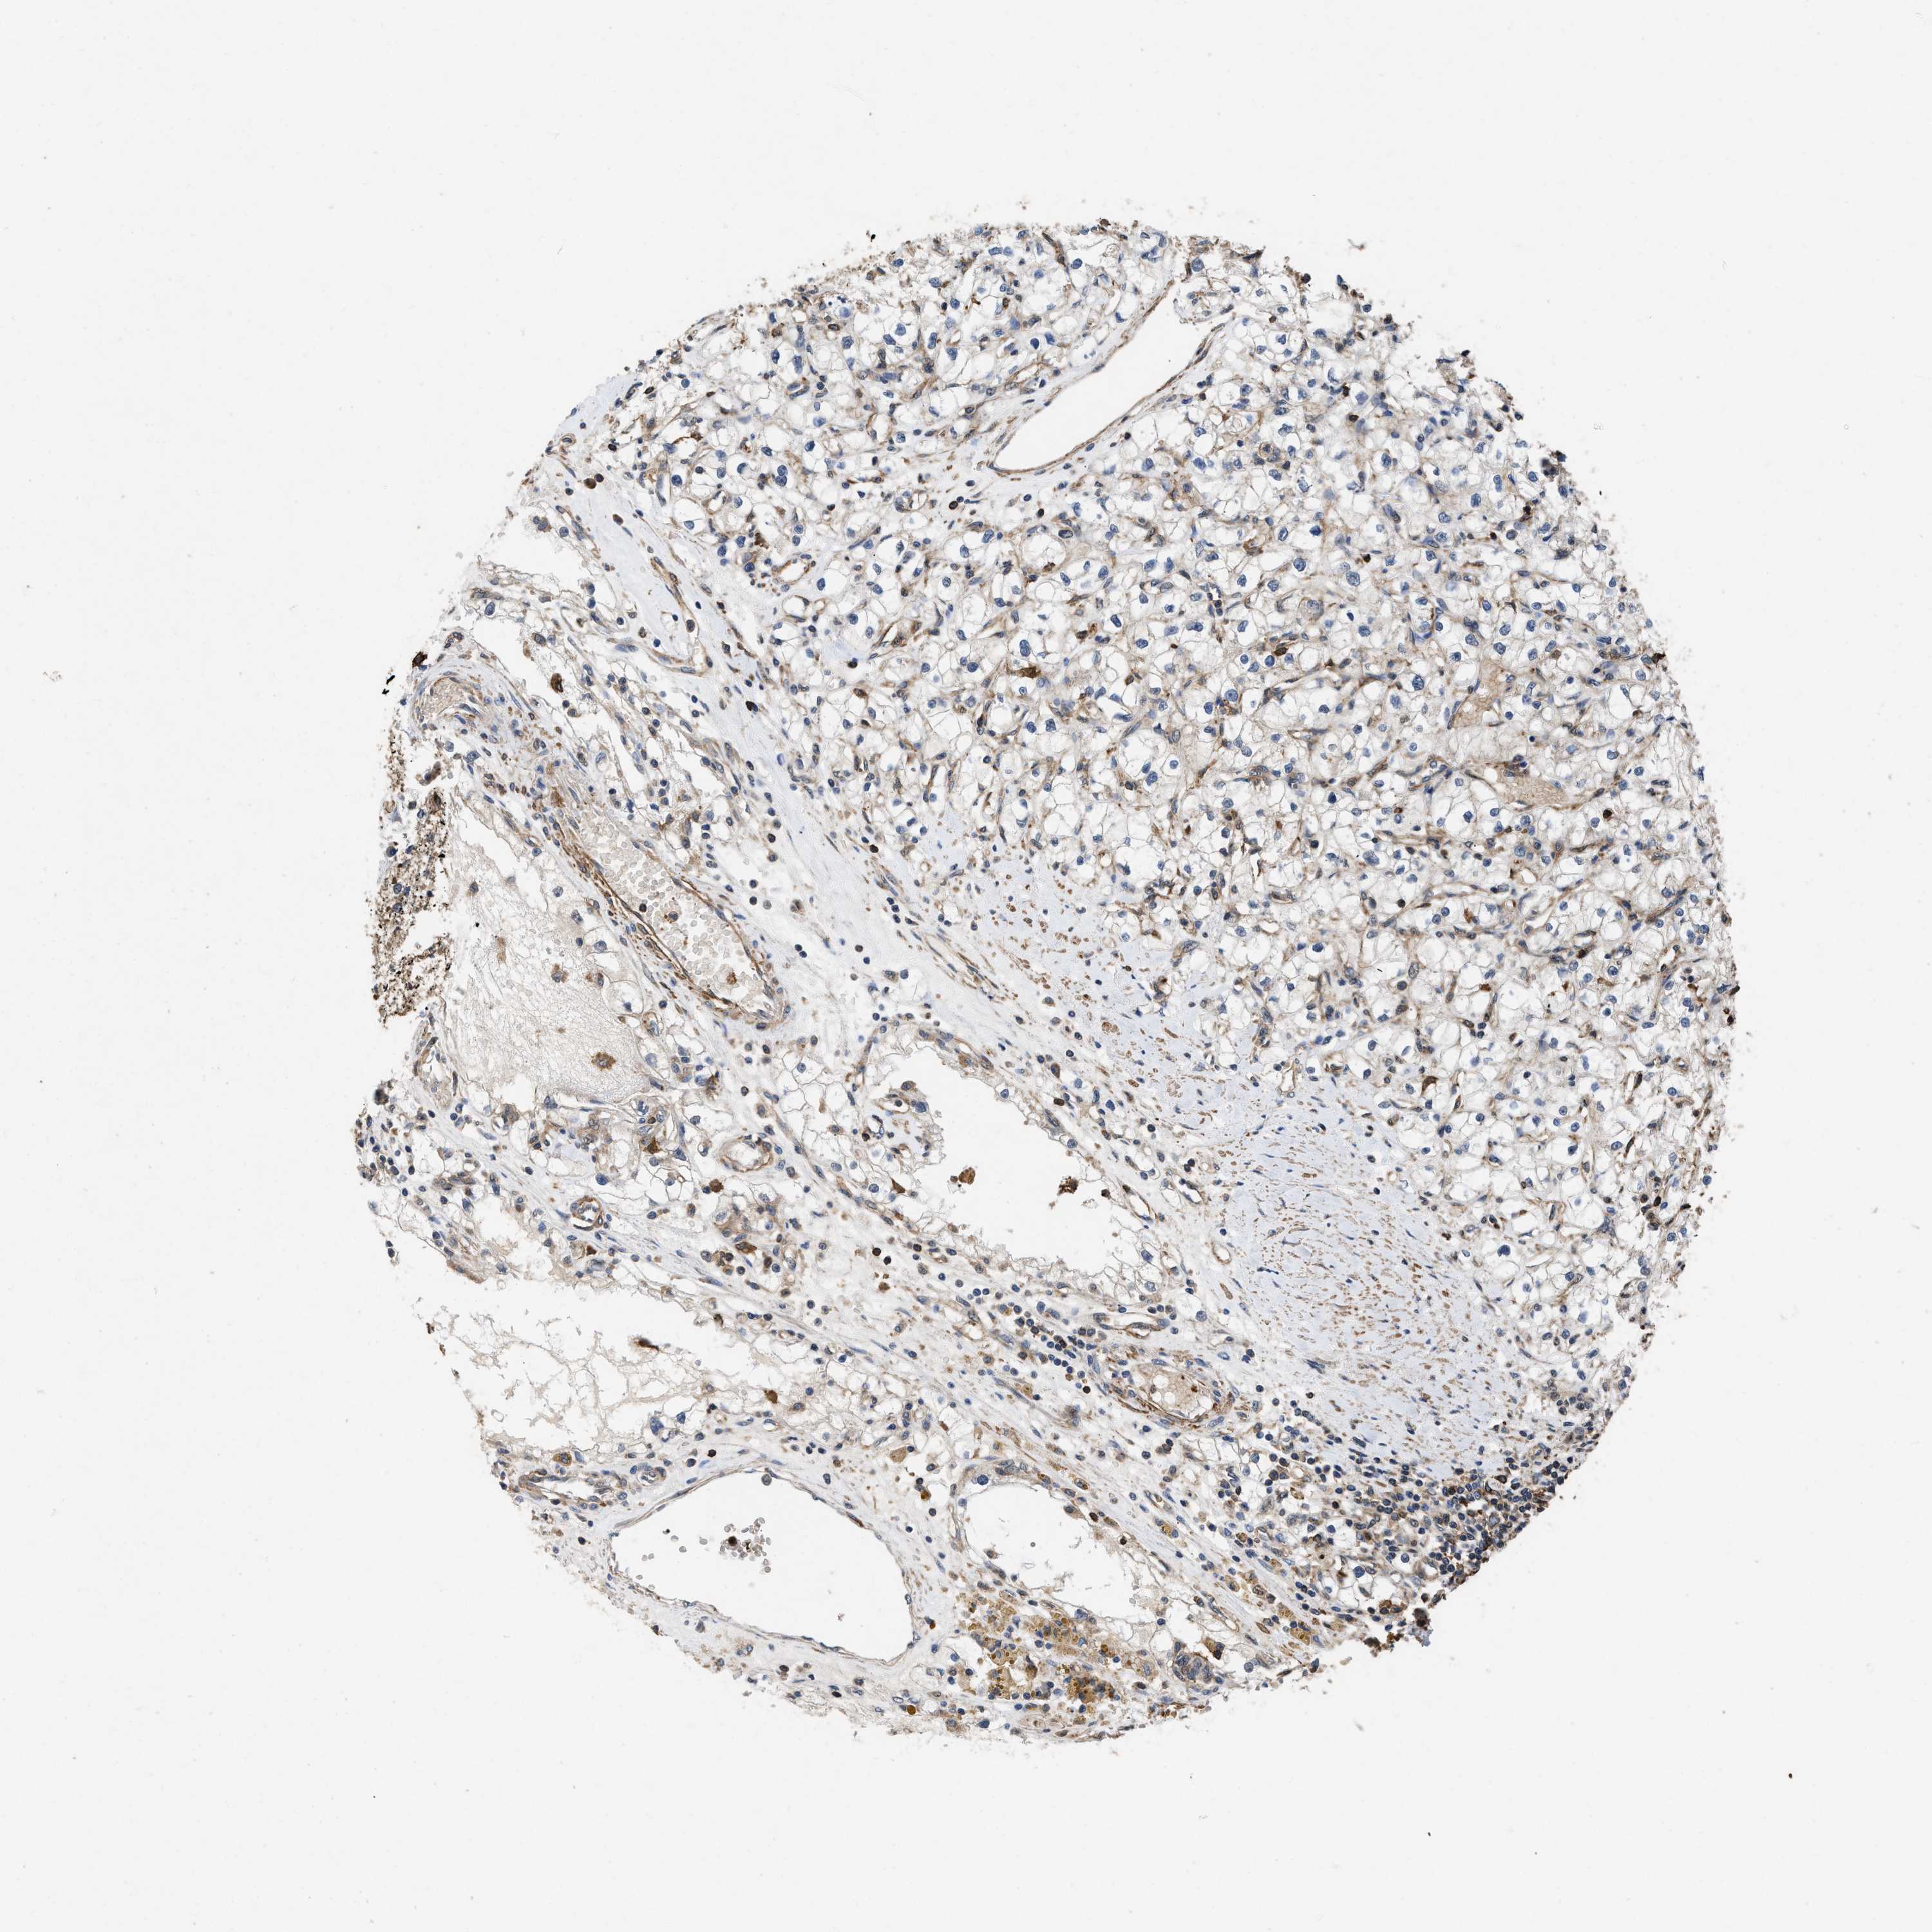

CANCER RENAL CANCER Show tissue menu

KICH TCGA KIRC TCGA KIRC VALIDATION KIRP TCGA PROTEIN RCC CPTAC PROTEIN EXPRESSION

KIDNEY RENAL PAPILLARY CELL CARCINOMA (TCGA) - Interactive survival scatter ploti

LINGO2 is not prognostic in Kidney Renal Papillary Cell Carcinoma (TCGA)